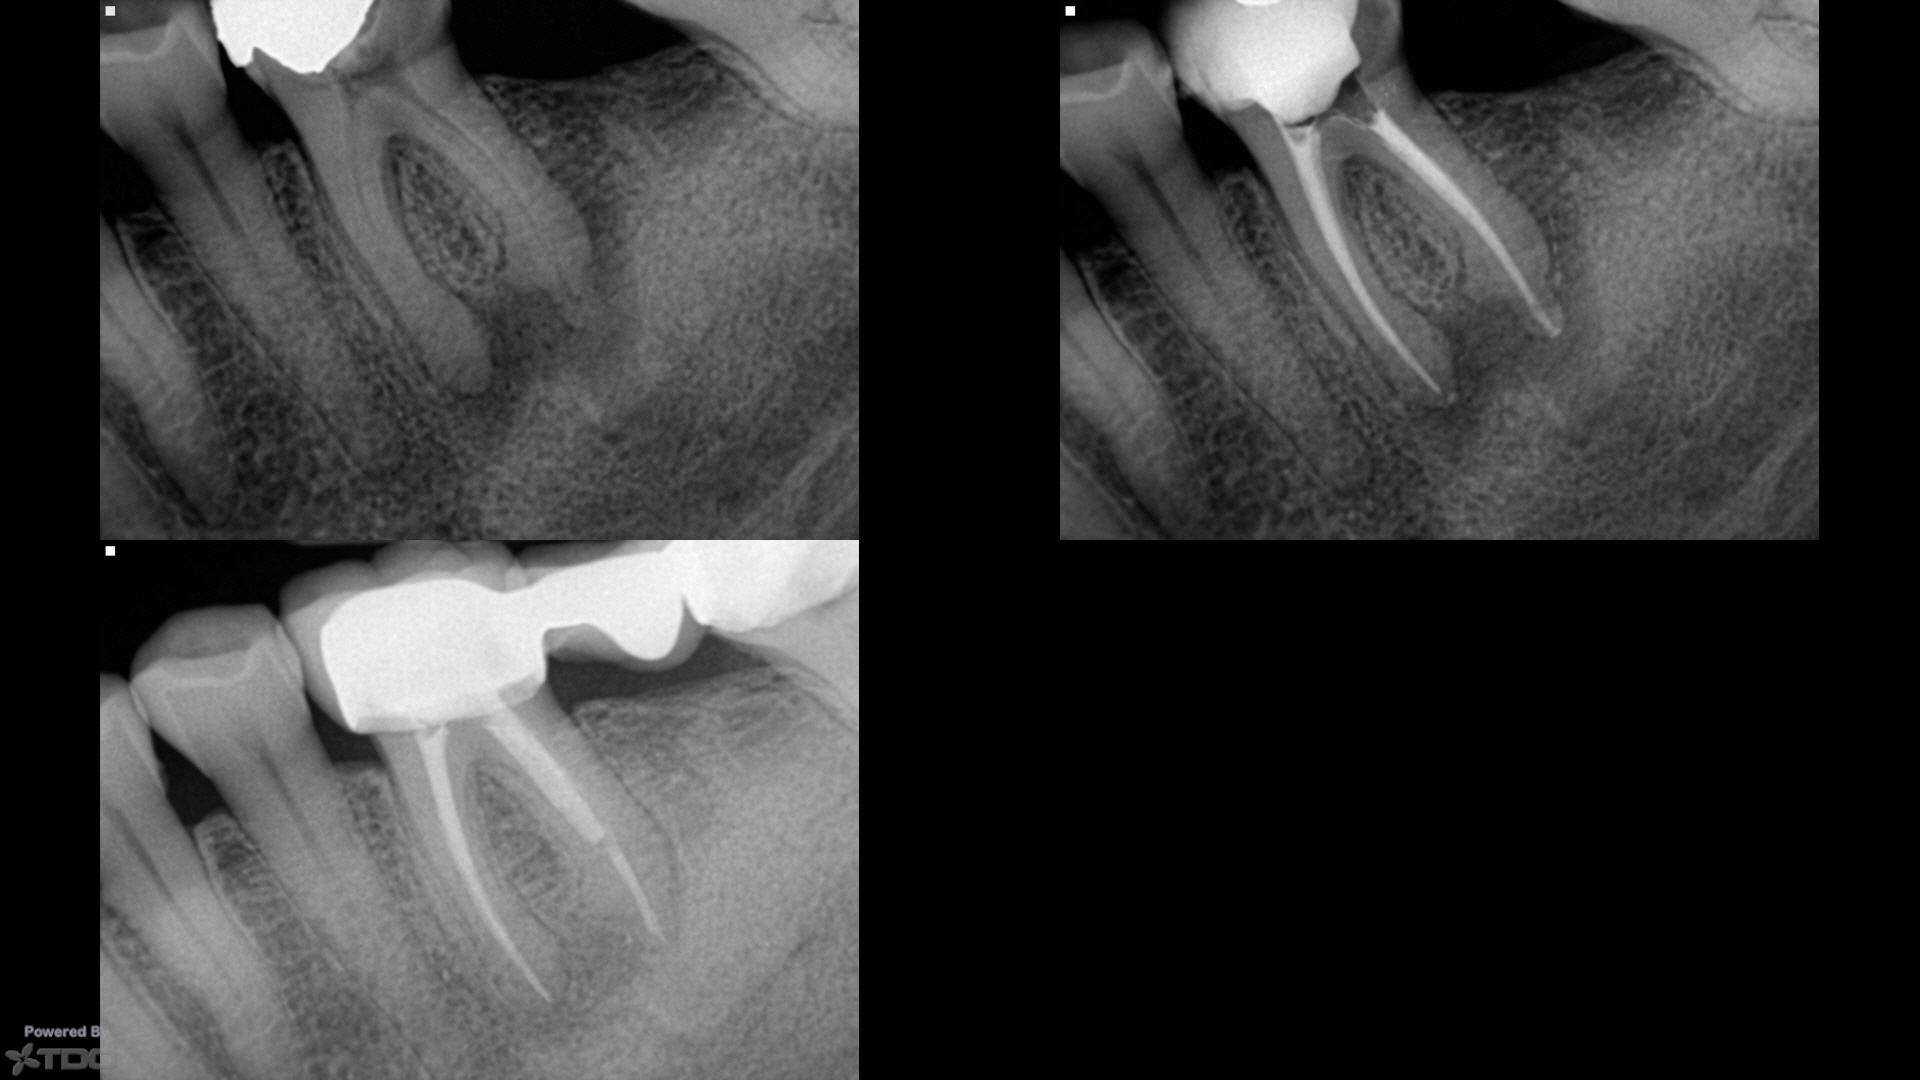

The process begins with the patient receiving local anesthesia to ensure their comfort throughout the treatment. Then, utilizing state-of-the-art techniques and advanced equipment such as digital imaging and operating microscopes, the endodontist meticulously removes the infected or damaged pulp from the tooth’s root canals while ensuring minimal discomfort for the patient.

These specialists alsouse their expertise to address complex cases involving intricate root canal anatomy or failed previous root canal treatments. Their precision and attention to detail enable them to effectively clean and disinfect the canals before filling them with biocompatible materials like gutta-percha.